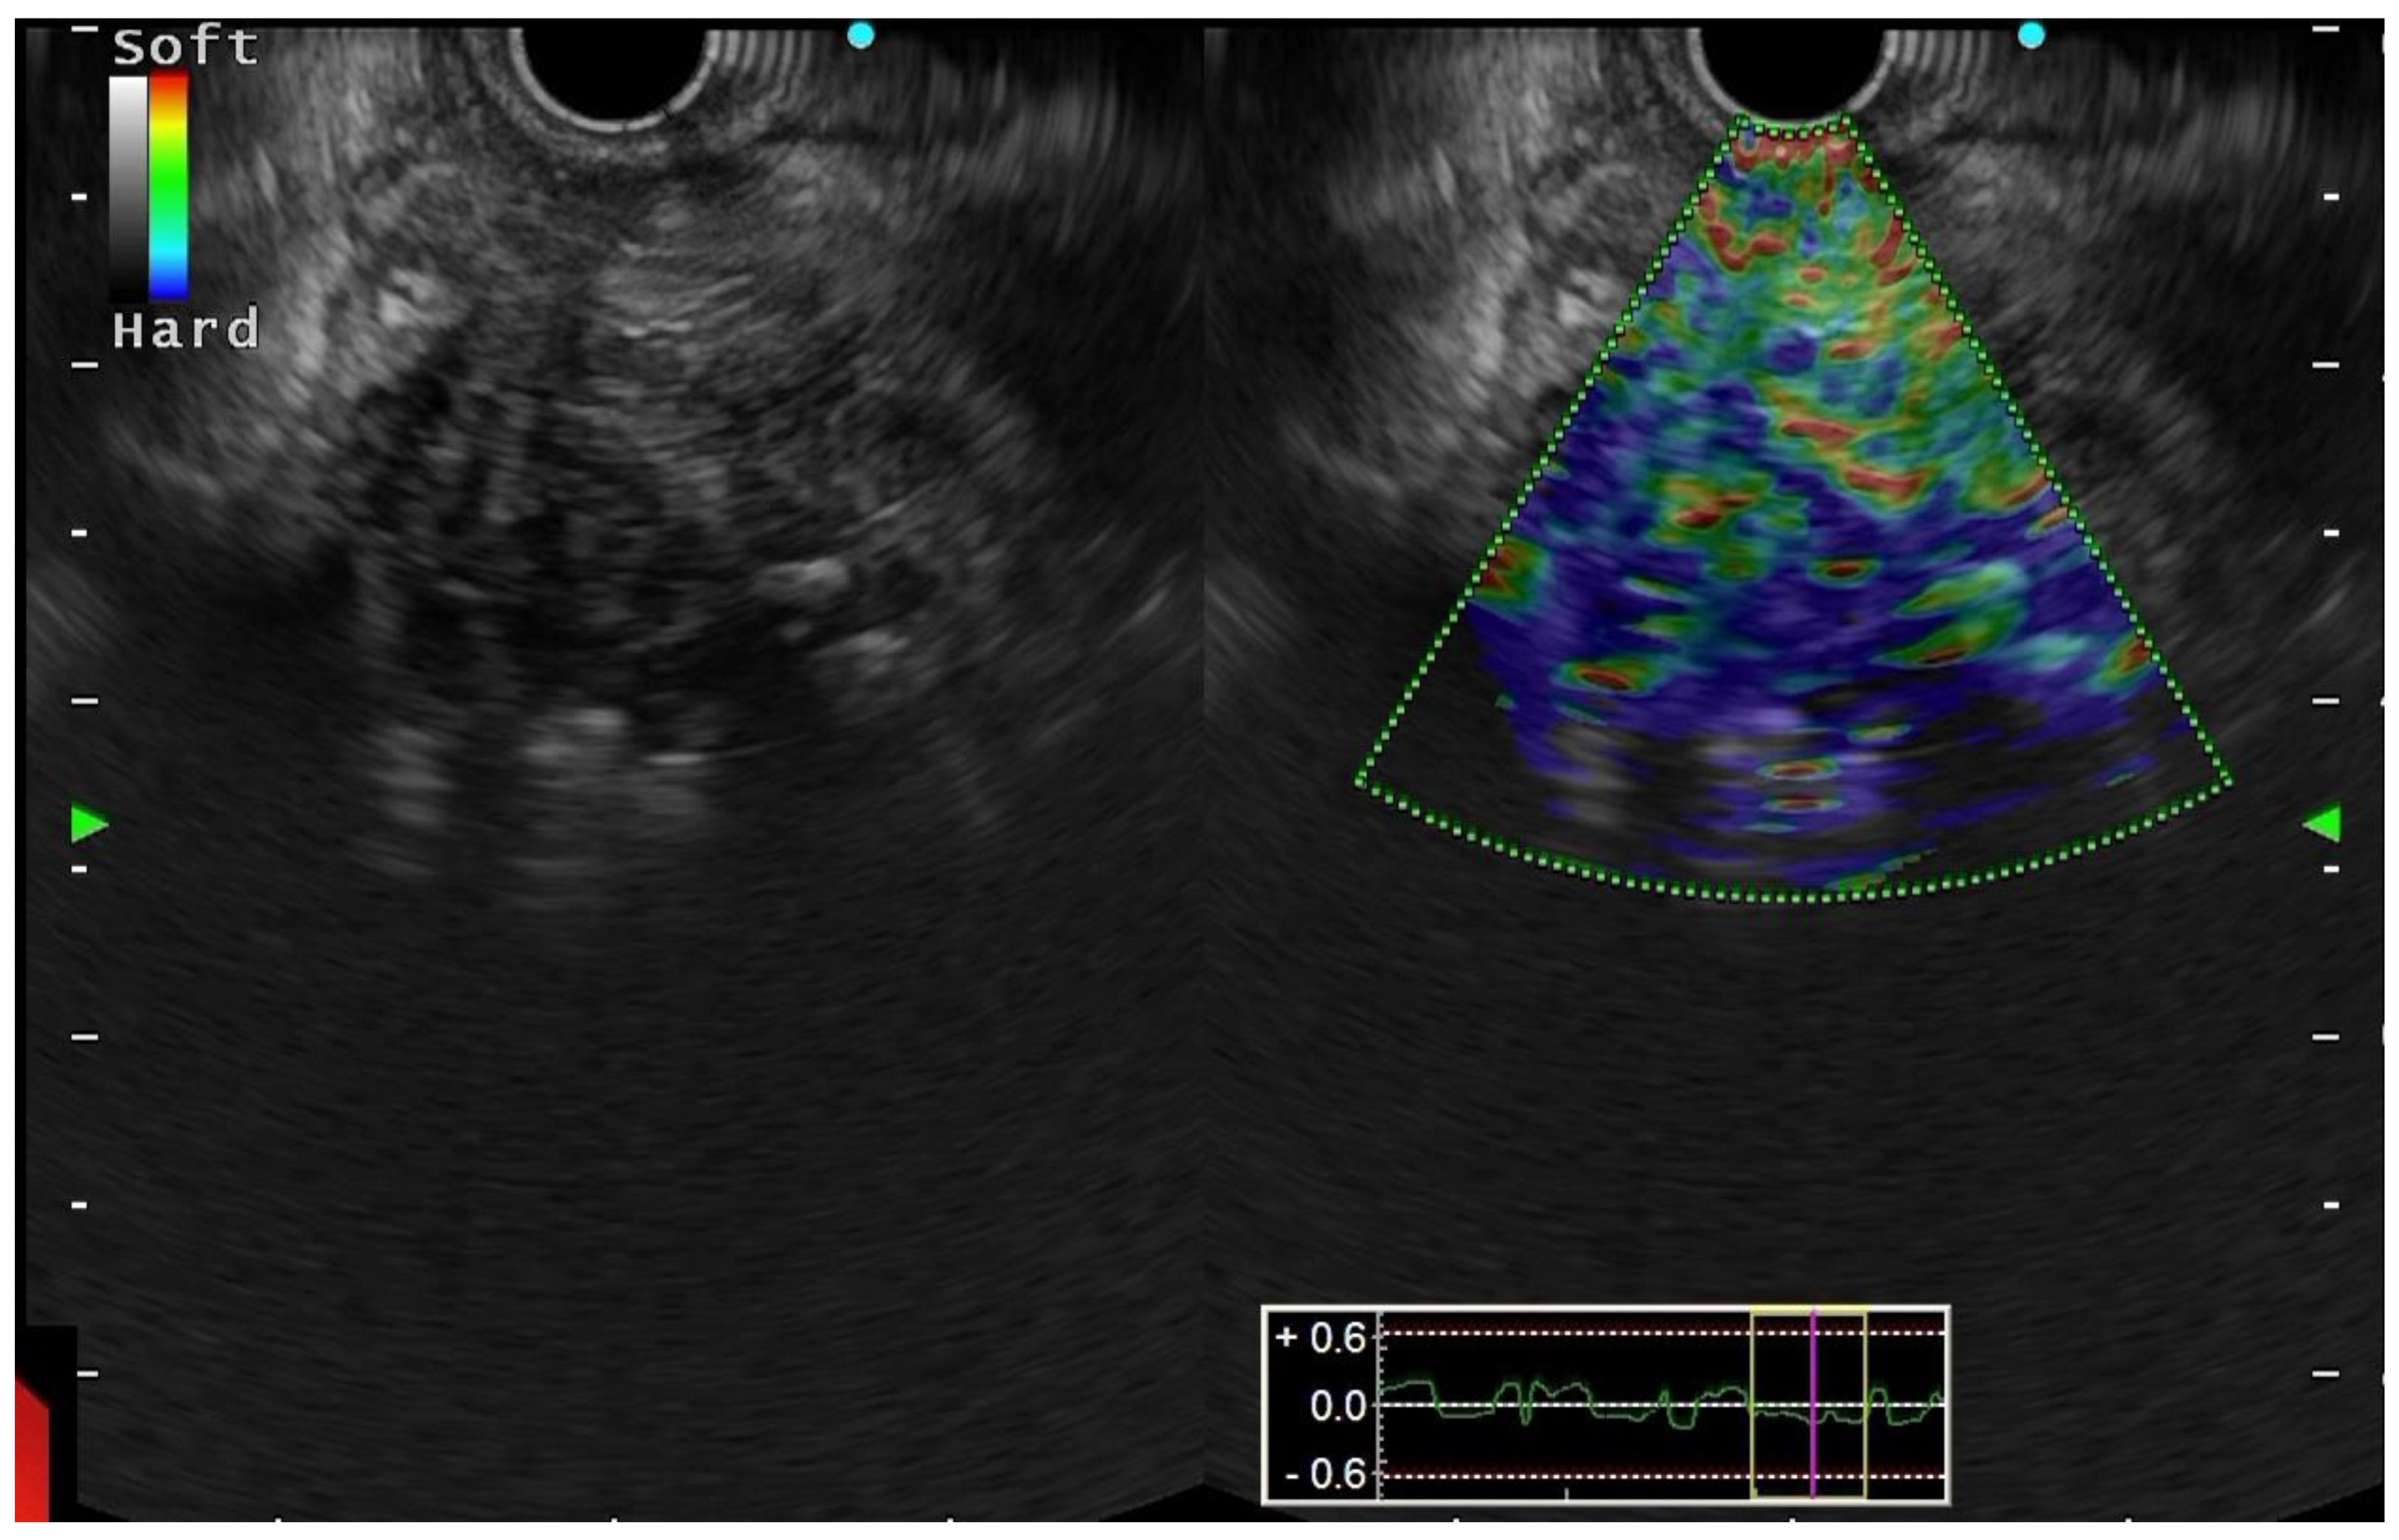

5.3. Endoscopic Modalities

5.4. Other Modalities